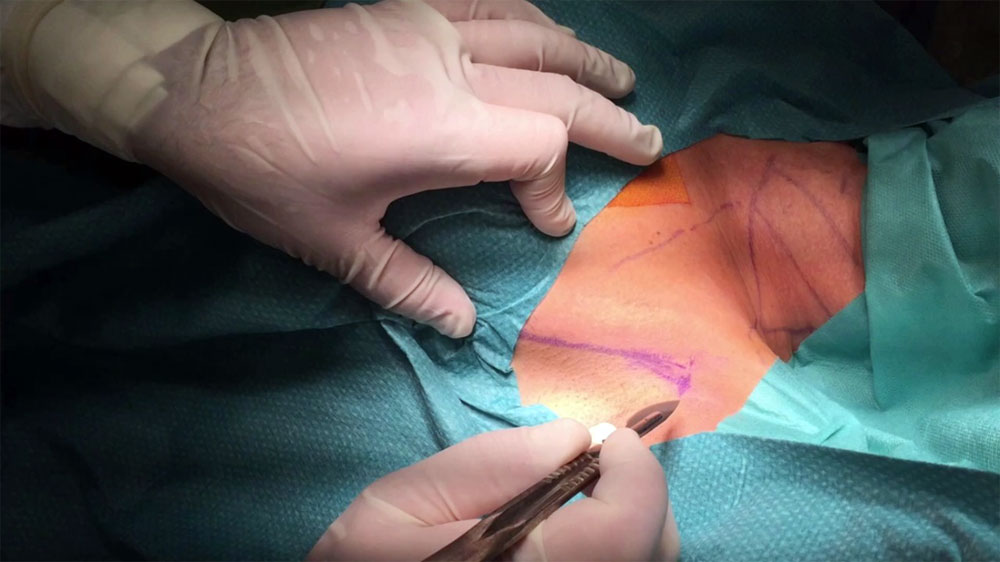

Пироговский Центр продолжает реализовывать план мероприятий в рамках федерального проекта «Борьба с онкологическими заболеваниями»

Врачи-онкологи Центра неоднократно освещали различные темы, касающиеся диагностики и лечения злокачественных новообразований, в средствах массовой информации.

Благодаря участию Центра в федеральном проекте «Борьба с онкологическими заболеваниями» ряд отделений Центра получили новое оборудование, необходимое для диагностики и лечения пациентов с подозрением или уже выявленным злокачественным новообразованием. В 2022 году запланирована организация Отделения лучевой терапии Центра.